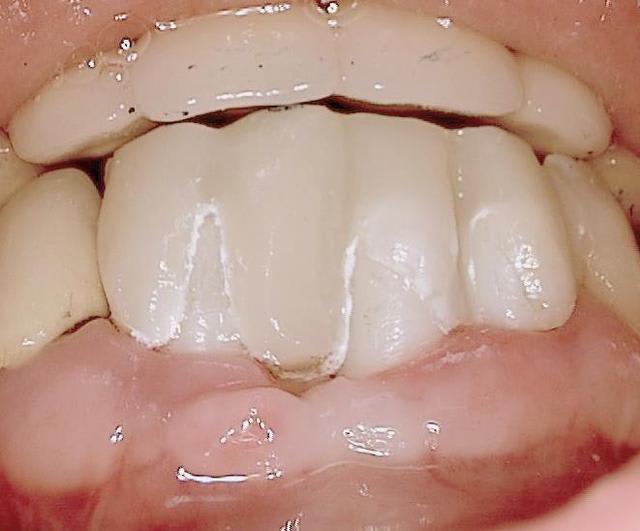

Folie1 ofu0m9 - Eugenol

Folie2 z7edyr - Eugenol

Folie3 aeqhya - Eugenol

Folie4 q9egfx - Eugenol

Folie5 icxmia - Eugenol